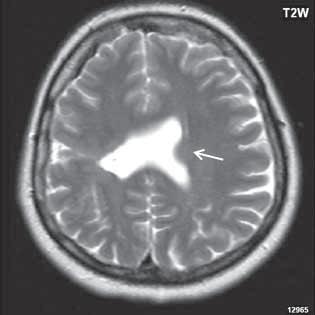

Obr. I.1.1d Fyziologické změny v závislosti na věku baze lební a corpus callosum, zvýšený signál v oblasti celé kosti klínové a klivu (žlutá kostní dřeň) (šipka), dochází k pneumatizaci a vývoji sinus sfenoidalis (přerušovaná šipka) ve 4 roce života